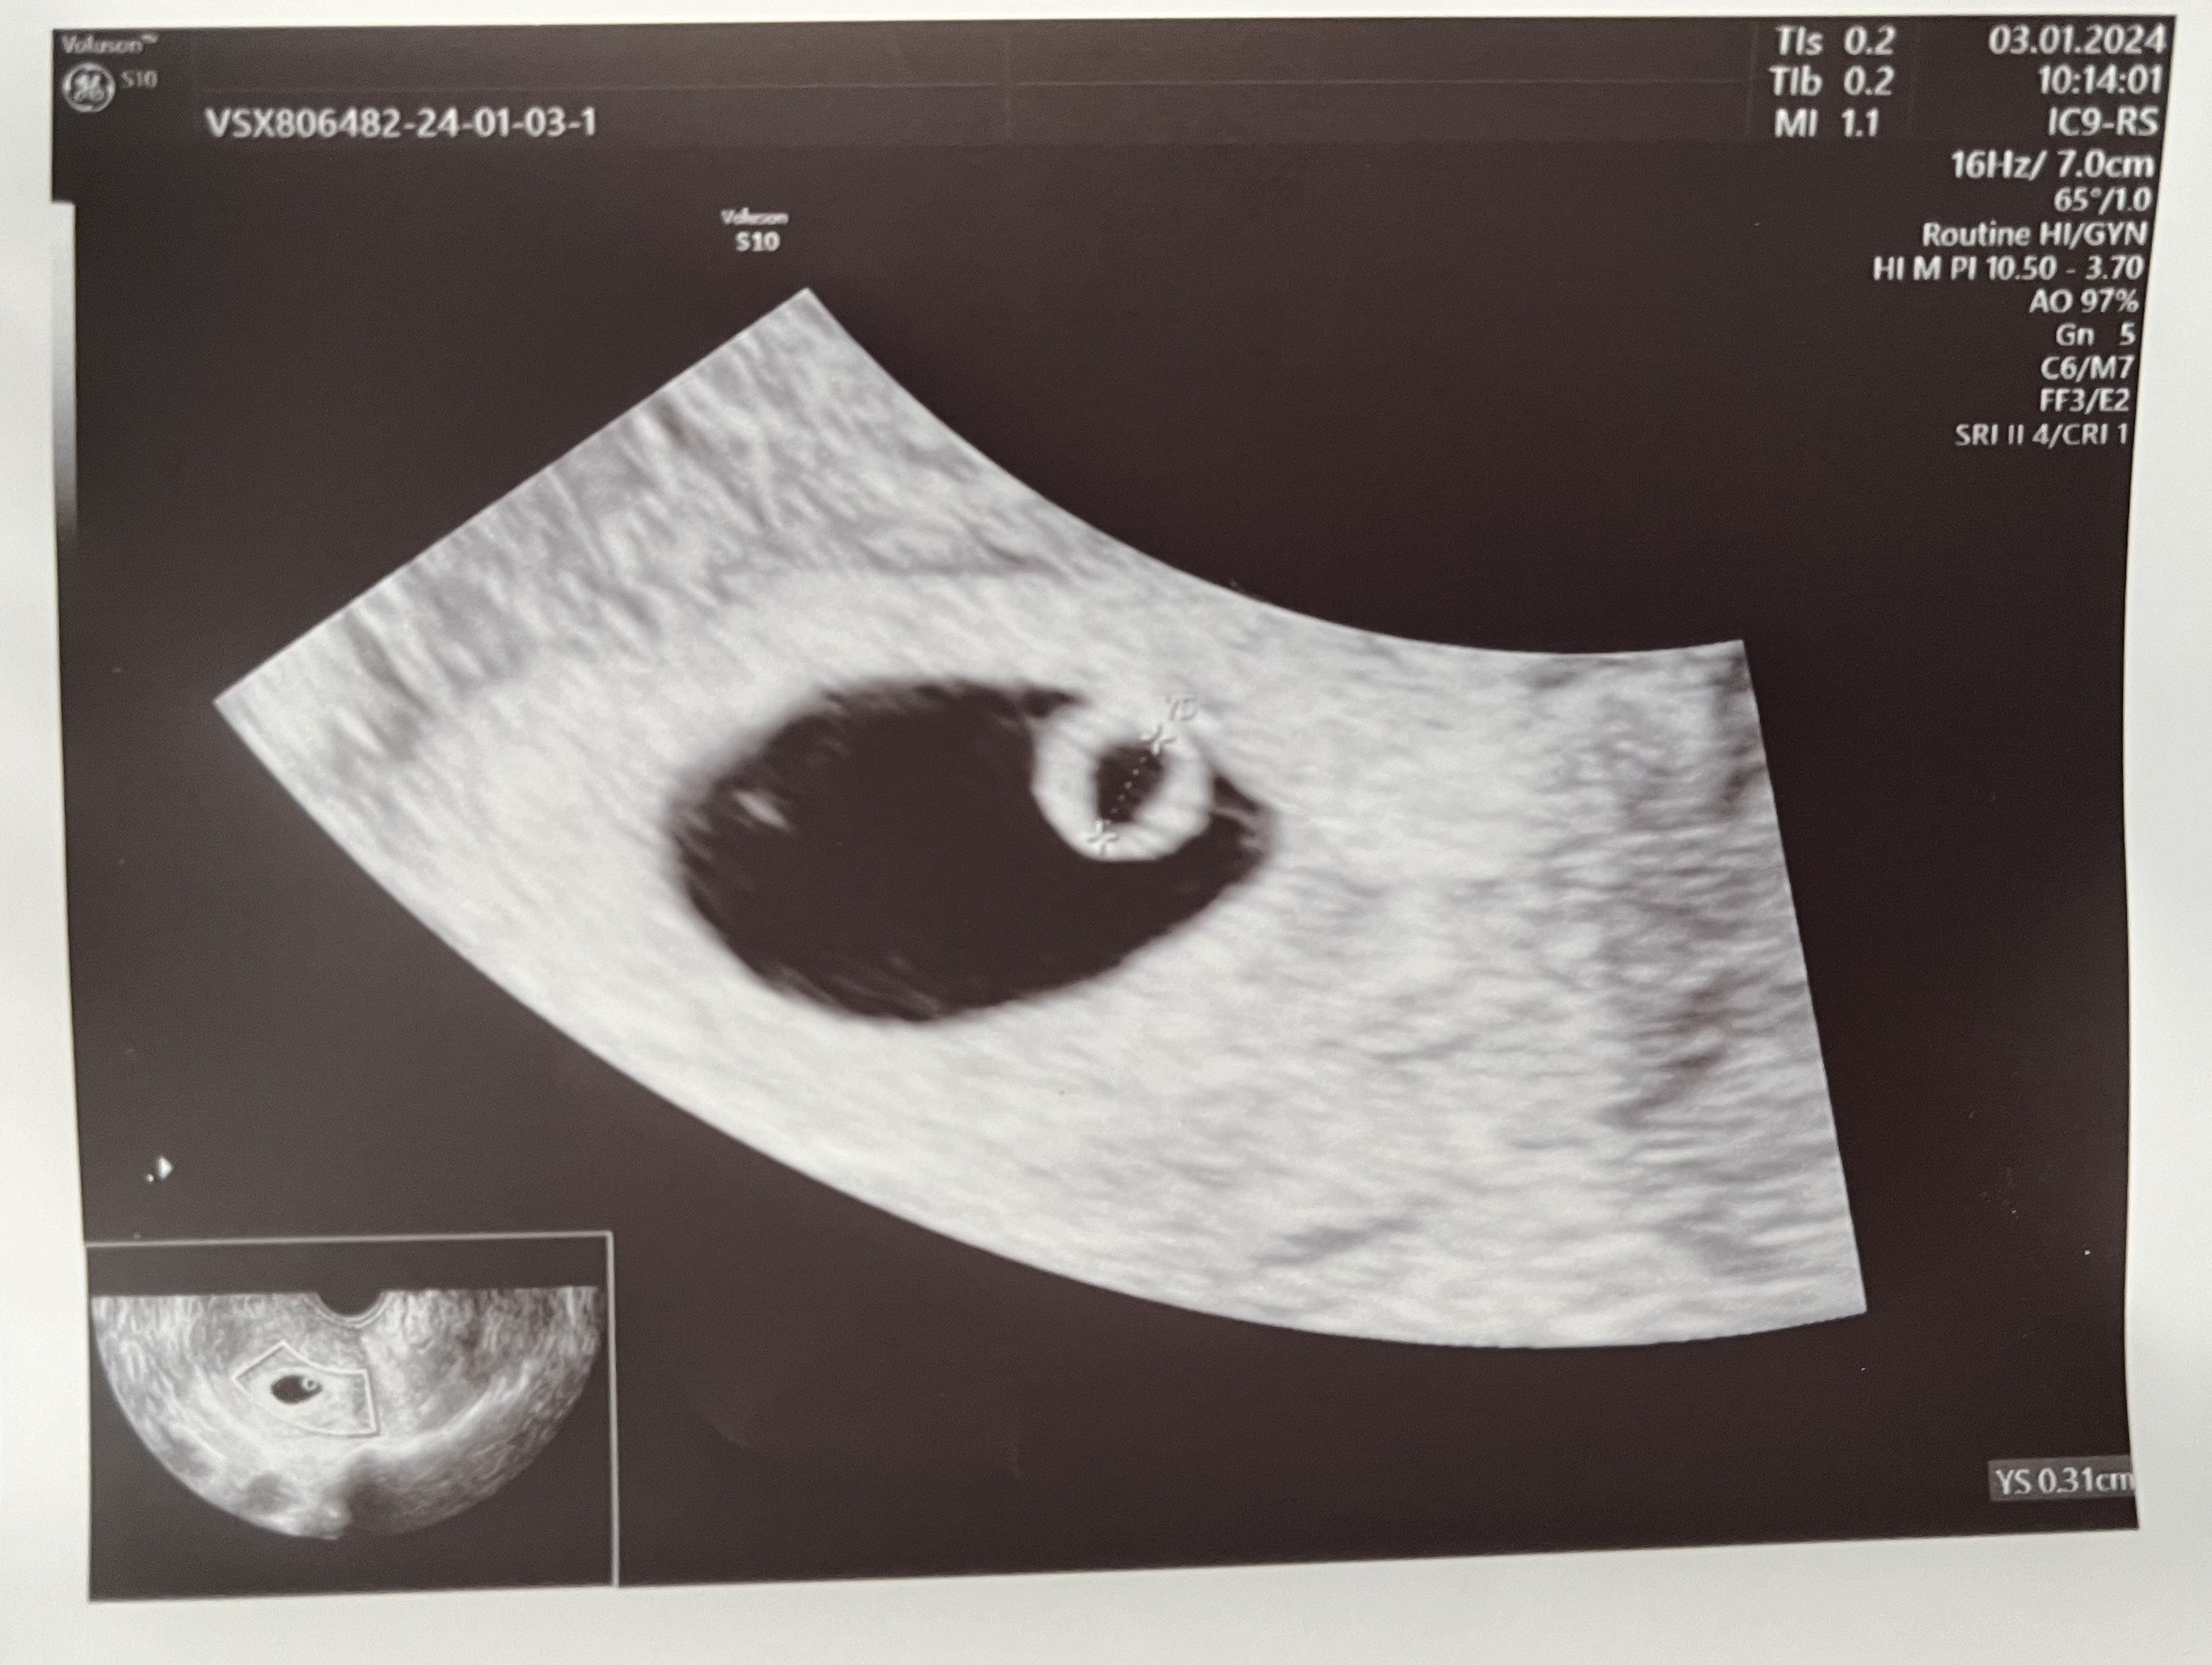

Na jedynym zdjęciu jakie mam nie widzę takiej informacji, ale podczas wizyty lekarz skomentował tylko, że pęcherzyk ciążowy jest w normie.Zobacz załącznik 1600206

Na zdjęciu wszystko wygląda super

Pęcherzyk żółtkowy piękny w super wielkości . Myślę że maluszek się gdzieś schował i zaraz się pojawi . cierpliwości . Ciąża nawet ta po invitro to nie matematyka ;)

Aktualizacja: 03.01. Beta powyżej 16 tys., progesteron 27,5. 05.01. Beta powyżej 22 tys., progesteron 49. Te moje wyniki to jakiś kosmos. Byle do piątku…